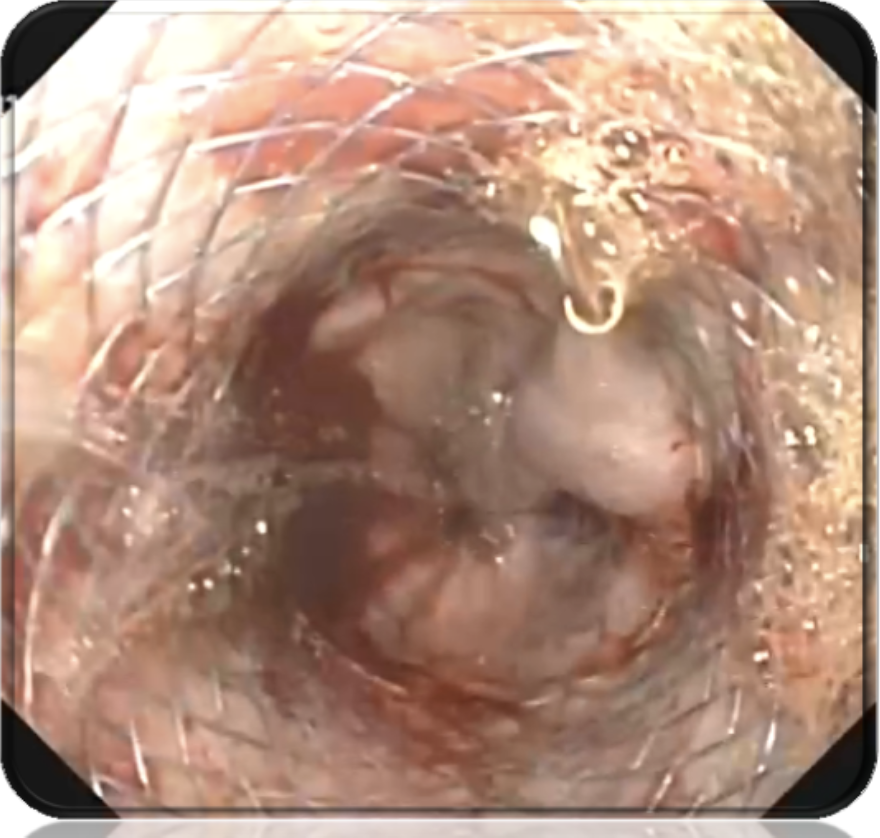

Исследования последних лет свидетельствуют о том, что при рефрактерном варикозном пищеводном кровотечении средством гемостаза столь же эффективным и более безопасным, чем баллонная тампонада зондом-обтуратором Sengstaken – Blakemore, могут быть пищеводные саморасширяющиеся нитиноловые стенты Danis. Однако, не смотря на рекомендации, выработанные в ходе целого ряда консенсусных встреч, эта позиция в лечебной программе варикозного кровотечения остается до конца не решенной (рис. 2).

Проанализированы результаты лечения варикозного кровотечения из пищевода, рефрактерного к медикаментозной и эндоскопической терапии у 59 больных внутрипеченочной портальной гипертензией (рис. 3).

Механический гемостаз в группе сравнения был достигнут в 33 (75,0%) клинических наблюдениях. В то же время у 11 (25,0%) пациентов наступил рецидив, в том числе у 9 (20,5%) сразу же после распускания баллонов, у 2 (4,5%) – после удаления зонда – обтуратора. В основной группе гемостаз был достигнут в 13 (86,7%) клинических наблюдениях. В то же время у 2 (13,3%) пациентов остановить кровотечение с помощью стента не удалось. Произошла дистальная миграция стента с потерей его тампонирующей функции (рис. 6).